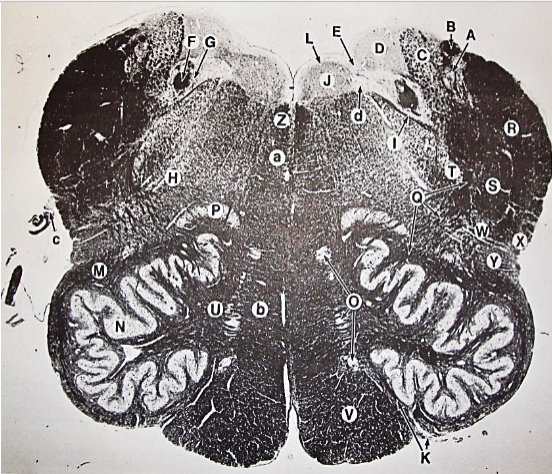

A

Lateral Cuneate nucleus

B

dorsal external arcuate fibers

C + D collectively

vestibular nuclei

C + D collectively

vestibular nuclei

E

dorsal motor nucleus of vagus nerve

F

solitary fasciculus

G

solitary nucleus

H

nucleus ambiguous

I

fascicles of glossopharyngeal nerve

J

hypoglossal nucleus

K

fascicles of hypoglossal nerve

L

dorsal longitudinal fasciculus

M

central tegmental tract

N

inferior olivary nucleus

R

inferior cerebellar peduncle

S

spinal trigeminal tract

T

spinal trigeminal nucleus

U

ventral trigeminothalamic tract

V

pyramidal (corticospinal) tract

W

rubrospinal tract

X

anterior spinocerebellar tract

Y

spinal lemniscus

Z

medial longitudinal fasciculus

a

tectospinal tract

b

medial lemniscus

c

vagus nerve

d

inferior salivatory nucleus

A + B collectively

vestibular nuclear complex

D

solitary fasciculus

E

solitary nucleus

F

nucleus ambiguous

G

fascicles of glossopharyngeal nerve

H

spinal trigeminal tract

I

spinal trigeminal nucleus

J

ventral trigeminothalamic tract

K

central tegmental tract

L

interior olivary nucleus

O

inferior cerebellar peduncle